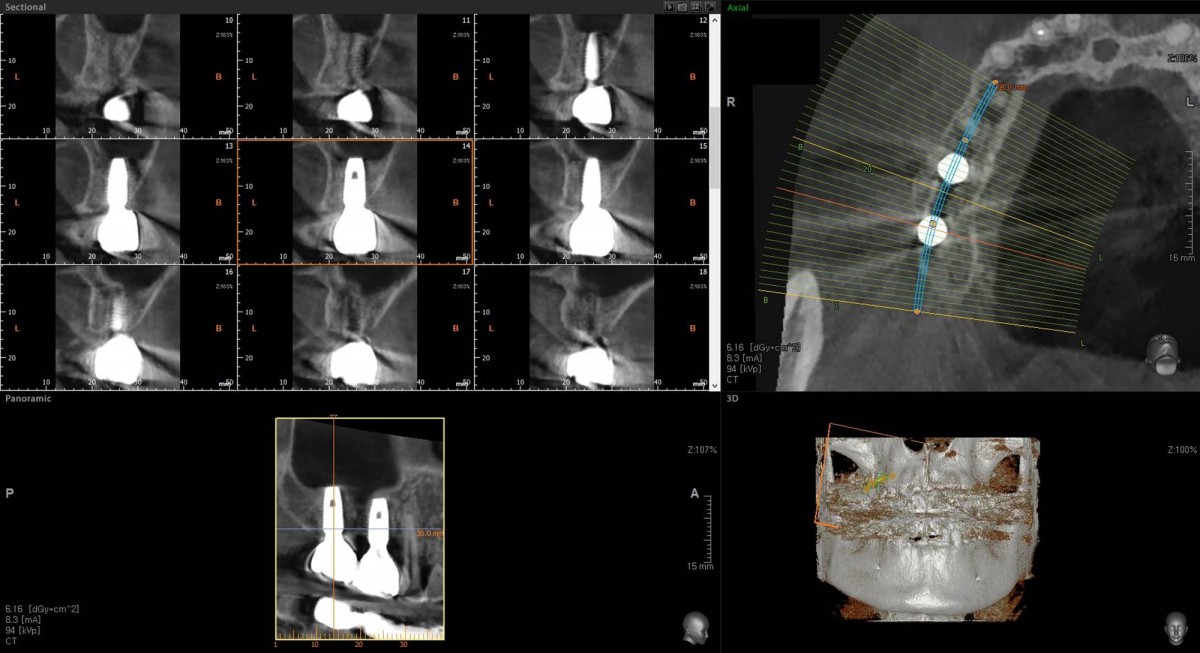

Socket Lift and Implant Placement in the right maxilla.

<GCacg> A 56-year-old male patient complained of pain in the right upper and lower jaws. And he wanted the upper first molar to be pulled out first.